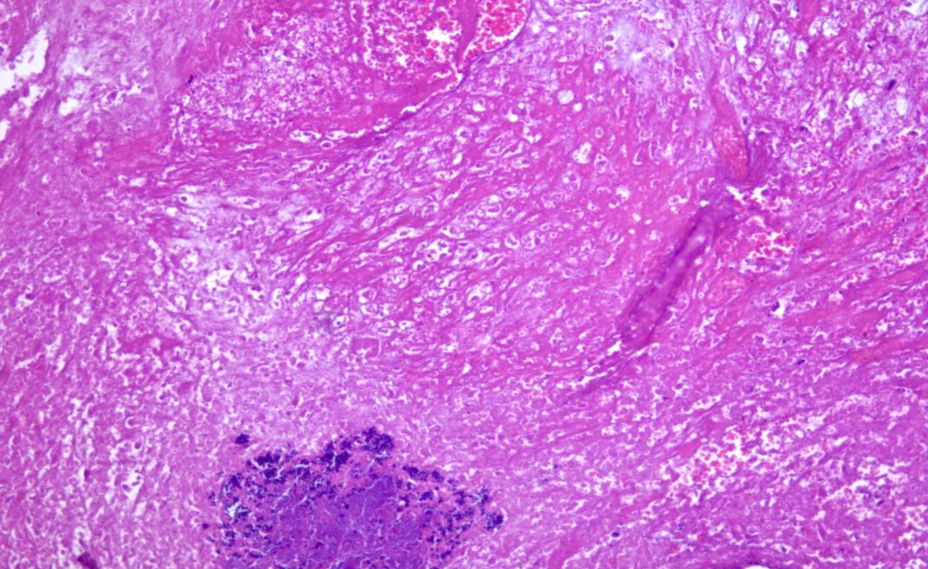

Some examined sections showed ulceration in the epidermal layer with extensive dermatitis that characterized by inflammatory cells infiltration (Fig. 3). Minimal pleomorphism was occurred and mitotic figures were few to absent. Inflammatory cells were infiltrating the dermis, which showing varying numbers of lymphocytes and neutrophils.